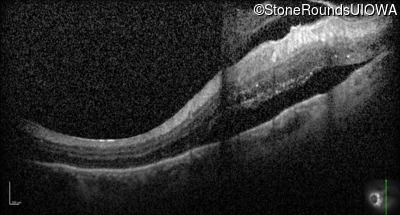

Optical Coherence Tomography - Right - 20/50 +2

Exemplar / OCT Stack